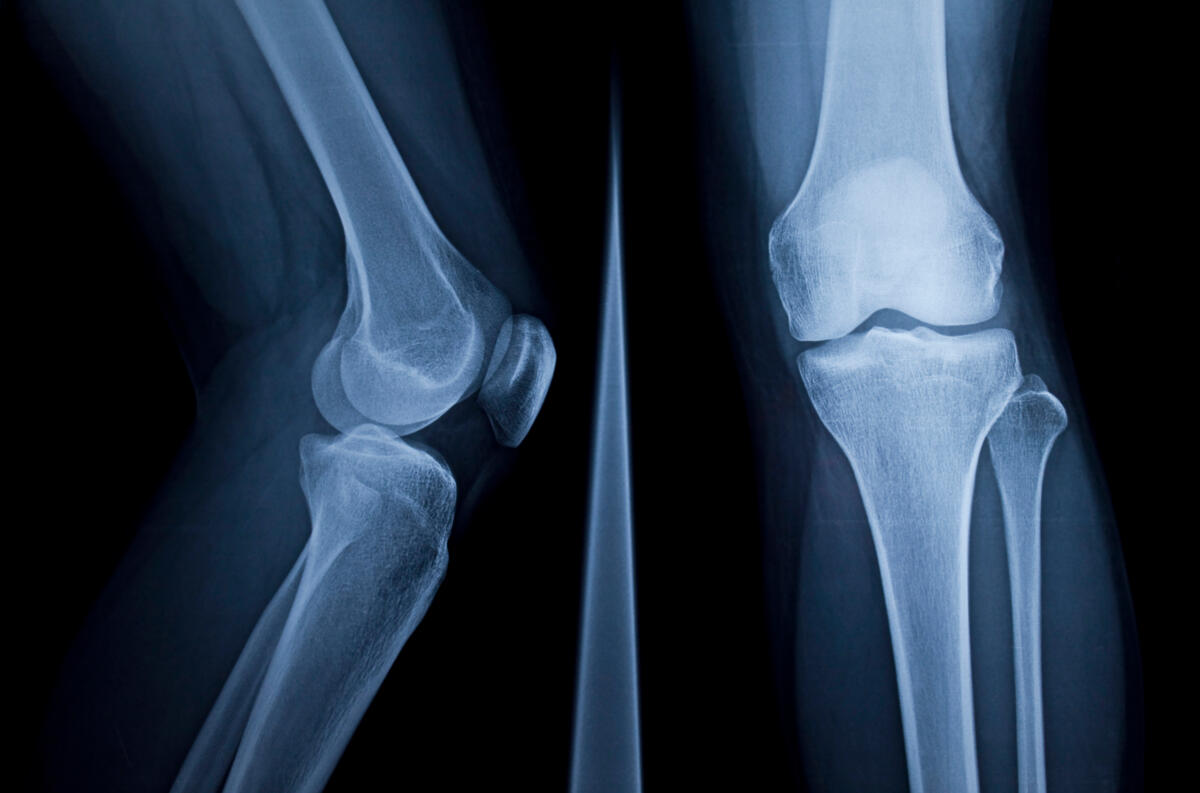

L’ostéomyélite chronique est un processus inflammatoire osseux souvent lent et avec des symptômes subtils, causé par un agent infectieux.

Le traitement de l’ostéomyélite chronique repose sur une prise en charge chirurgicale permettant de débrider les fragments d’os nécrotique (séquestres) et de réaliser des prélèvements osseux afin d’instaurer une antibiothérapie ciblée sur l’agent pathogène.